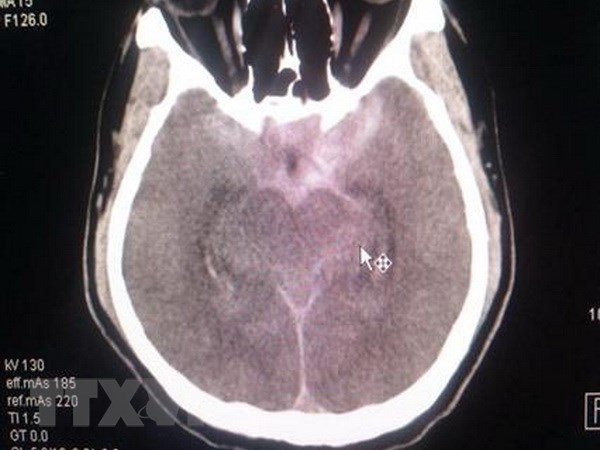

Hình ảnh CT sọ của bệnh nhân trước can thiệp. (Ảnh: TTXVN phát)

Kết quả CT-scan sọ não và DSA mạch máu não cho thấy bệnh nhân bị xuất huyết khoang dưới nhện do vỡ túi phình đốt sống bên phải.